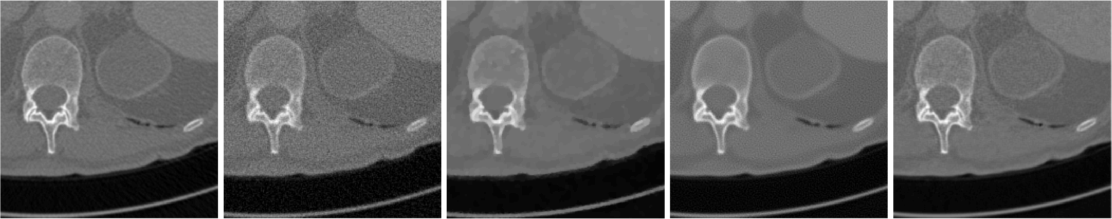

Fig. 2 (a) illustrates the reconstructions of a test image for case when measurement is noiseless. FBP is dominated by line artifacts, while TV satisfactorily removes these but blurs the fine structures. FBPConv and RPGD, on the other hand, are able to reconstruct these details. The zoomed version shows that RPGD is able to reconstruct the fine details better than the others. This observation remains the same when the measurement quality degrades. Fig. 2 (b) shows the reconstructions for 45-dB and 40-dB noise levels. In these scenarios, RPGD40 is significantly better than both FBPconv40 and TV.

Fig. 3 compares the reconstructions for the case when the noise levels are 45 dB and 35 dB. It is visible that FBPconv40 results in a noisy image and TV is again blurred. RPGD40 retains the fine structures and is the best performer.